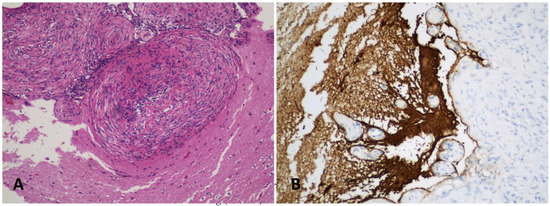

2. Case Presentation